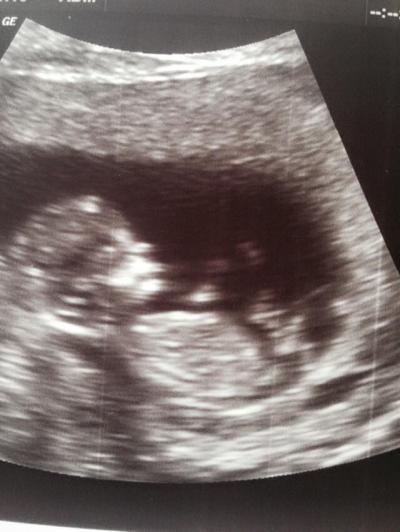

Heute bei 12+3 Ersttrimesterscreening und Nackenfaltenmessung. Alles super bzw unauffällig, 6,7 cm ist es groß und ein totaler Turner. Heute im Profil konnte man alles super sehen: Nase, Hände, Füße. Auch die Hebamme habe ich heute kennengelernt und wir haben uns gut verstanden und sehen uns dann jetzt vor jedem Arzttermin. Sie hat mir auch gleich einen Tee gegen meine Wassereinlagerungen mitgegeben oder wie sie meinte "Riecht wie Heu, schmeckt wie Heu - wirkt aber" - das hoffe ich jetzt einfach mal. Der nächste ist schon in drei Wochen, weil mein Arzt dann Urlaub hat.

Huhu Das hört sich doch alles super an;) so soll es auch sein :) Wie heißt der Tee denn??? Würde mich echt interessieren Und du hast wirklich ein sehr schönes bild:)))) Lg